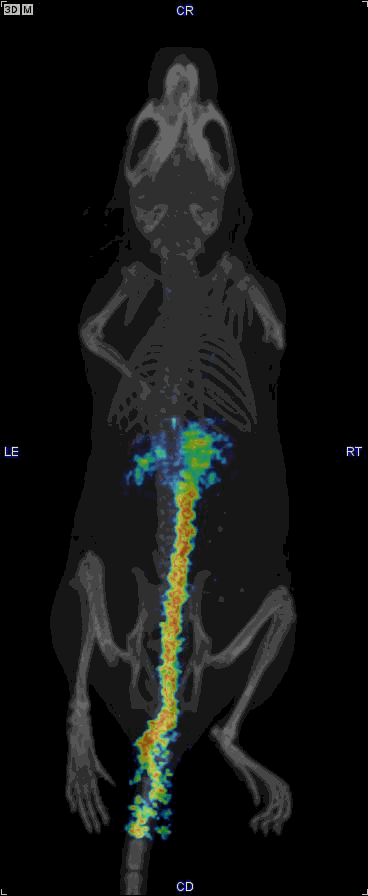

Gallery

This is a gallery of images and videos from various projects etc.